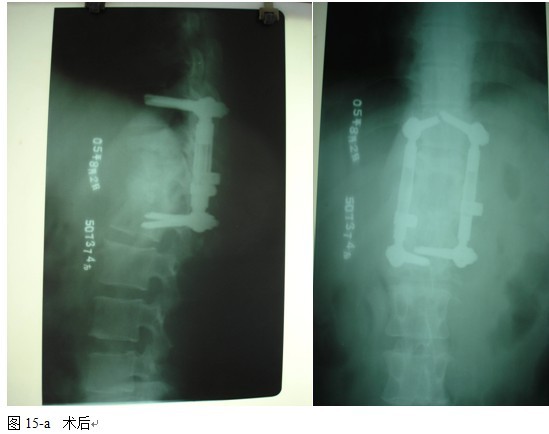

本组手术用时间3~4h , 平均3.5h 。术中出血300~500ml , 平均约350ml 。术后症状完全缓解,无神经功能障碍加重等并发症,1例营养差的老年患者伤口出现窦道,1例因肝功能差,术后未口服抗痨药,伤口出现窦道,经换药后二期愈合,其余病例伤口均一期愈合。马尾神经受损的患者术后基本恢复正常。术后一周后凸角平均 5.4°后凸畸形平均矫正90%以上, 最终后凸角平均8.3°,后凸角度平均丢失4.2°。随访3个月有87%(40/46)有骨痂形成,6个月91.3%(42/46)明显骨性愈合(见图),其余4例9-12个月内愈合,随访时间3-32个月,平均11个月,46例患者中2例在术后2个月和3个月时背部形成脓肿,换药后治愈。2例出院1月后并发结核性脑膜炎,治疗后好转。1例因椎弓根钉偏外,刺激神经根,5个月后从侧方脱出,疼痛加重,因前后路植骨完全愈合,取出后症状完全缓解。

4.1腰椎结核手术治疗中应用内固定的必要性和安全性:为了预防和矫正畸形,稳定脊柱,减少结核的复发率以及提高病变节段的融合率,让患者早期下床功能锻炼, 国内外学者将内固定用于脊柱结核的手术治疗中,取得了令人满意的效果[4、5、6、7、8、9、10]。通过本组病例观察,我们发现内固定的应用有着重要的作用,内固定不但可以预防,矫正后凸侧弯畸形,而且畸形的矫正率明显提高,未见畸形加重和矫正的明显丢失,还能使病变节段在术后即刻获得足够的稳定性, 为脊柱融合和结核病灶的静止提供一个良好的力学环境,促进了植骨融合,未见植骨块的吸收,移位和假关节的形成,术后结合支具治疗,大大缩短术后卧床时间,简化术后护理,利于患者全身情况的改善及后续康复治疗。